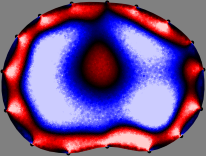

Figs. 3 and 4 compare the performance of the proposed FER method in (20) with the standard regularized least-squares method ((19) when is the identity matrix). The regularization parameter of the standard method was heuristically chosen for its best performance, and the parameter of the FER method was set to be one of three different values . The injection current was 1 mA at 100 kHz, and the frame rate was 9 frames per second. The reference frame at was obtained from the maximum expiration state. The measured data, , represent the voltage differences between each time and . The blue regions, which denote where conductivity decreased by inhaled air, increased during inspiration and decreased during expiration. The FER method with was clearly more robust than the standard method that produced more artifacts originated from the inversion process.

| Standard | |

||||||||||

| FER () | |

| FER () | |||||||||||